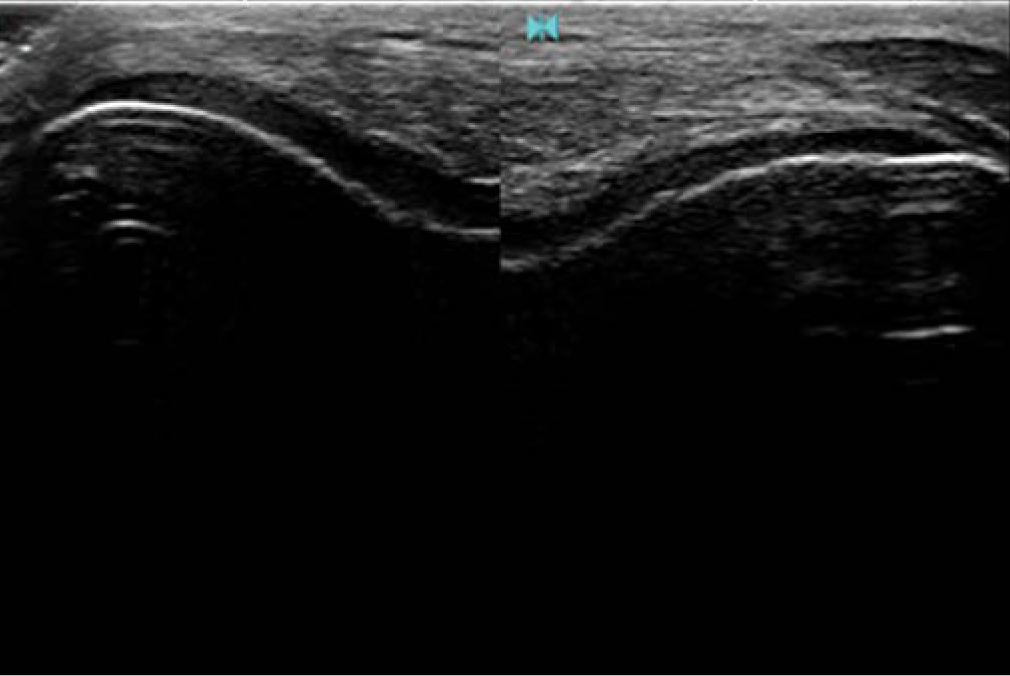

HONDA HS-2200 with 6.0/8.5/11.00 MHz HLS-584M transducer (Honda, Japan) was used for the measurement of articular cartilage covering the medial and lateral femoral condyle. The knee was positioned in the maximum flexion. The transducer was applied transversely just above the patella, perpendicular to the surface of the femoral condyles. The obtained images were used to measure the thickness of homogeneous low echoic or anechoic cartilaginous structure using ultrasound software (Fig. 1). Good repeatability of the measurement of the articular cartilage covering the lateral and medial femoral condyle was shown(16). Both limbs were evaluated by the same operator.

An ultrasound scan showing an articular cartilage layer covering the femoral condyle